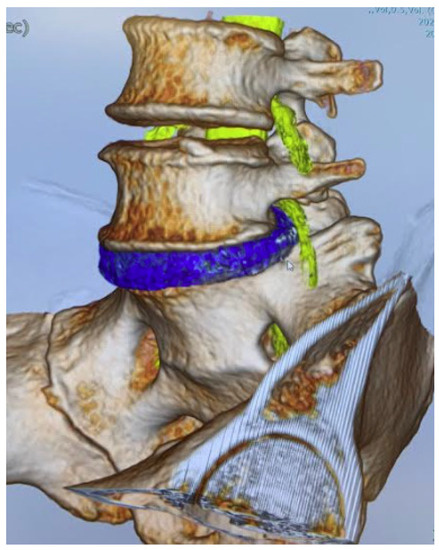

2.3. CT-MRI Fusion Image

2.4. Evaluation of Merged Images

3.3. Possible Needle (1 mm) Passage at 60° and 45°

3.4. Possible Dilater (5 mm) Passage at 60° and 45°